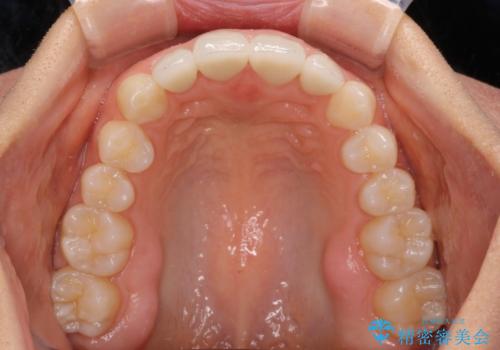

矯正治療後は、仮歯とした上顎前歯をオールセラミッククラウンにて補綴治療を行うこととしました。

日本と海外を拠点に仕事をされていらっしゃるため、数ヶ月治療があいてしまうことがあり、期間はかかりましたが、2年間で望み通りの前歯に仕上げることができました。